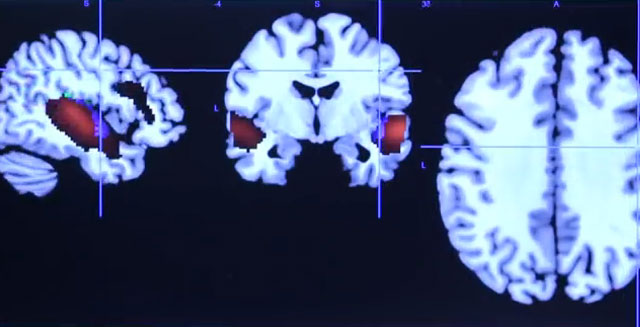

languages It is curious to know how the acquisition of new language activates

the same brain areas of reward as those that respond to stimuli such as sex,

food or gambling. Those responsible for this finding, Published in the

journal Current Biology , conclude that when learning new words and

their meaning not only activate the cortical circuits of language, but also

the cerebral areas of the vertical striation, one of the main areas within

the motivational and Reward, which “shows a possible emotional aspect

in the development of language,” explains Antoni Rodríguez Fornells,

one of the authors of the research. And they precisely conclude that that

motivation to learn new language - that is maintained in the time - is one

of the main reasons that takes to people to want to learn languages.

After analyzing by magnetic resonance how they learned the subjects under

study new terms in an invented language, It was found that the memory was

greater when words had been learned through gestures and images compared to

when only the method of listening and reading had been used.